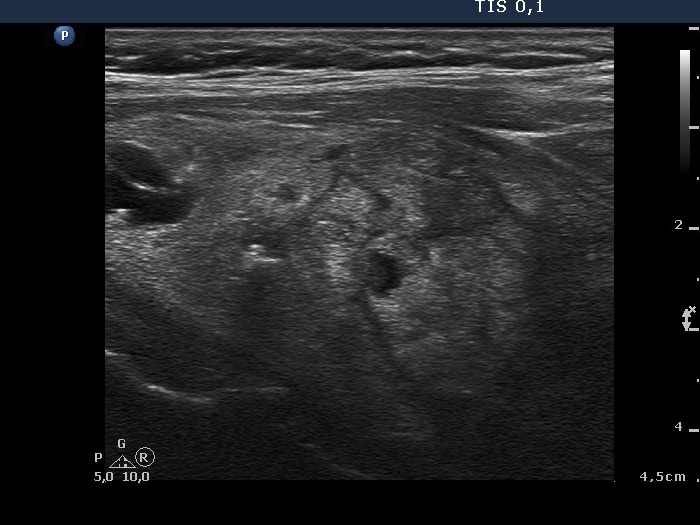

Follow-up investigation 8 month later (second row of images)

Clinical data: the patient had no complaints.

Palpation: the nodule in the right lobe was significantly smaller compared with first examination.

Functional state: euthyroidism (TSH 0.96 mIU/L).

Ultrasonography. The thyroid was echonormal. The nodule was composed of multiple echonormal discrete lesion and lacked cystic fluid. The volume was 1/8 of the pretreatment size.

Suggestion: yearly follow-up.